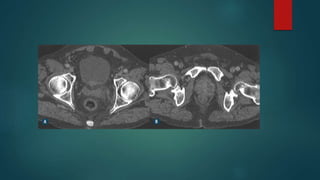

PÓS OP COM RECIDIVA/ REMANESCENTE

Pós – radio*